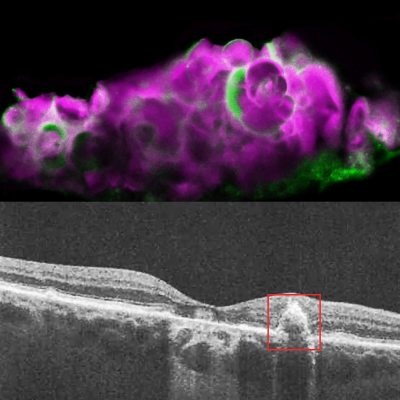

Top: HAP spherules (pink) and amelotin protein (green) in soft drusen from eye with dry AMD. Bottom: OCT image of eye with dry AMD, showing soft drusen beneath the retinal pigment epithelium. Image credit: Dinusha Rajapakse, NEI

Recently, researchers found a calcium-containing mineral compound called hydroxyapatite (HAP) in dry AMD deposits. HAP is a key component of tooth enamel and bone. Small balls of HAP filled with cholesterol, called spherules, were found only in drusen from people with dry AMD, and not in those with wet AMD or without AMD.

To verify that their cell culture model was accurately representing dry AMD, the researchers examined human cadaver eyes with dry AMD, wet AMD, or without AMD. They found HAP and amelotin only in the eyes with dry AMD, and not in the other eyes. While amelotin was found sometimes in areas of dry AMD without drusen, it was primarily present in soft drusen areas with large deposits of HAP.